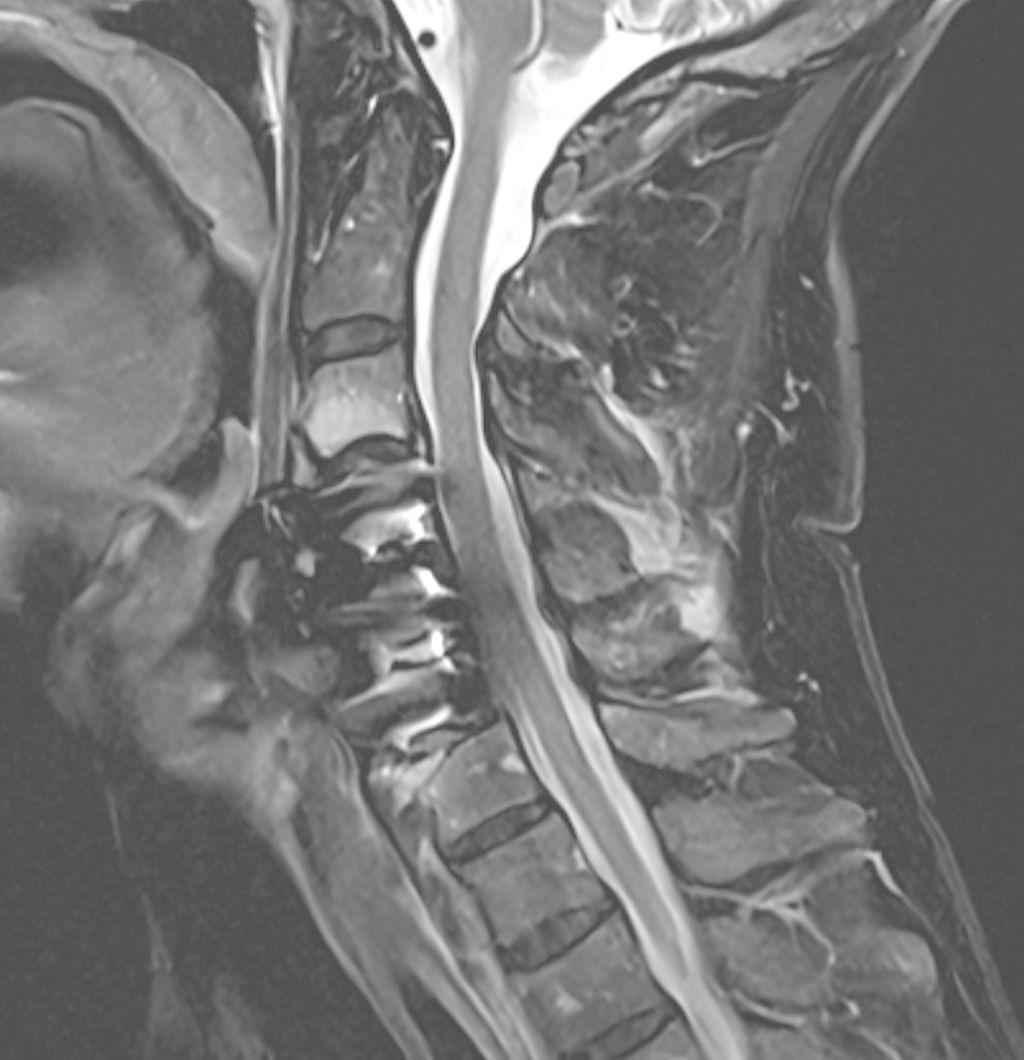

Fallbeispiel 1

Beispiel für die Implantation zervikaler Pedikelschrauben. In diesem Fall kam es bei einem 61-jährigen Patienten 10 Jahre nach anteriorer zervikaler Diskektomie und Fusion (ACDF) C4/5 und ventraler Verplattung C4–6 zu einer Ankylosierung auch von C6/7. Nach Sturz kam es zu einer Fraktur bei C6/7 mit begleitender Bogenfraktur und auch Beteiligung der dorsalen Ligamenta (Abb. 1 und 2). Klinisch bestanden ausgeprägte Nackenschmerzen und kein neurologisches Defizit. Es wurde die Indikation der dorsalen Verschraubung von C4 auf Th1 gestellt. Intraoperativ wurde routinemäßig zusätzlich eine kleine Referenzschraube in einer Lamina – entfernt von der Dornfortsatz-Referenzklemme für die Navigation – gesetzt. Mit dieser konnte intraoperativ die Genauigkeit der Navigation exakt überprüft werden (Abb. 4 und 5). Mittels navigierter High-Speed-Fräse wurden die Schraubenkanäle vorgebohrt (Abb. 6), im Anschluss wurde der Bohrkanal ausgetastet und die Schrauben wurden implantiert. Abbildung 7 zeigt eine Röntgenkontrolle 3 Monate postoperativ.